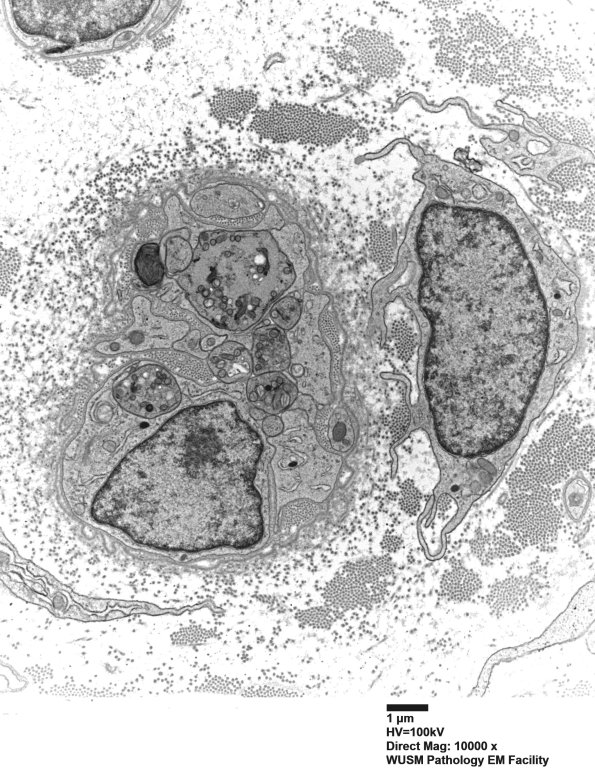

A macrophage approaches a collection of degenerating unmyelinated axons.